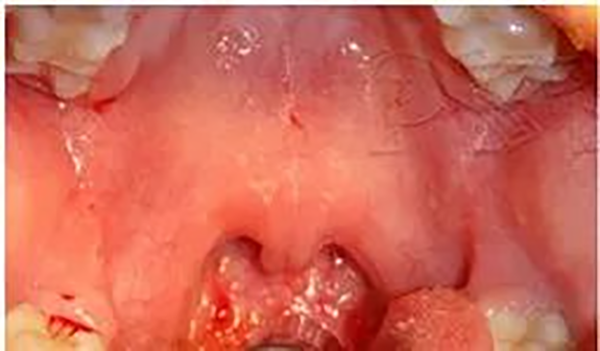

腭隐裂是腭裂的一种分型,属于发育异常导致的结构异常,典型表现包括:腭垂分叉、硬腭后缘切迹、软腭基层中线透亮影。

图2 腭隐裂的典型临床表现